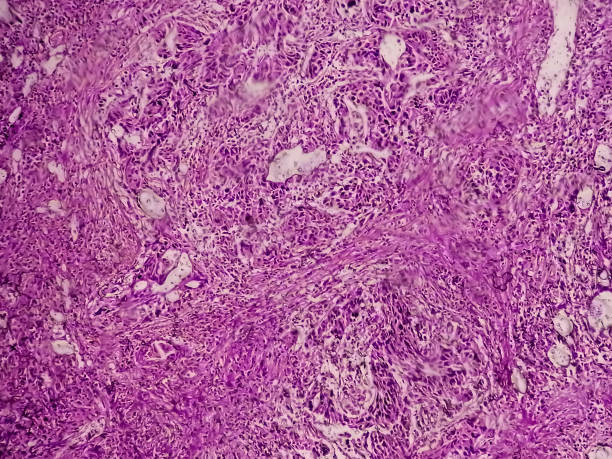

방광암 초기증상 10가지 자세히 알아보기

방광암은 초기에 증상이 뚜렷하지 않아서, 발견되기 전까지 오랜 기간 동안 증상이 없을 수 있습니다. 이로 인해 진단이 늦어져 치료가 어려워질 수 있습니다. 그러므로, 방광암의 초기증상을 잘 알고 있어야 증상이 나타났을 때 빠르게 대처할 수 있으며, 조기 발견과 치료로 인한 예후 개선 가능성이 큽니다. 또한 방광암은 흡연, 화학 물질 노출, 방광염 등의 위험 요인에 노출되면 발생할 가능성이 높습니다. 따라서 위험 요인에 노출되는 직업이나 환경에서 근무하는 사람들은 방광암에 대한 예방과 조기 발견에 더욱 신경써야 합니다.